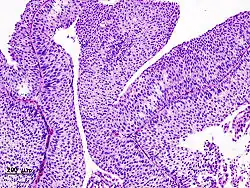

Histopathology of transitional carcinoma of the urinary bladder. Transurethral biopsy. Hematoxylin and eosin stain.

Transitional refers to the histological subtype of the cancerous cells as seen under a microscope.

The 1973 WHO grading system for transitional cell carcinomas (papilloma, G1, G2 or G3) is most commonly used despite being superseded by the 2004 WHO[14] grading for papillary types (papillary neoplasm of low malignant potential [PNLMP], low grade, and high grade papillary carcinoma). High-grade carcinoma typically displays more pleomorphism, multiple mitoses, euchromatin and relatively prominent nucleoli, and uneven distribution of nuclei.